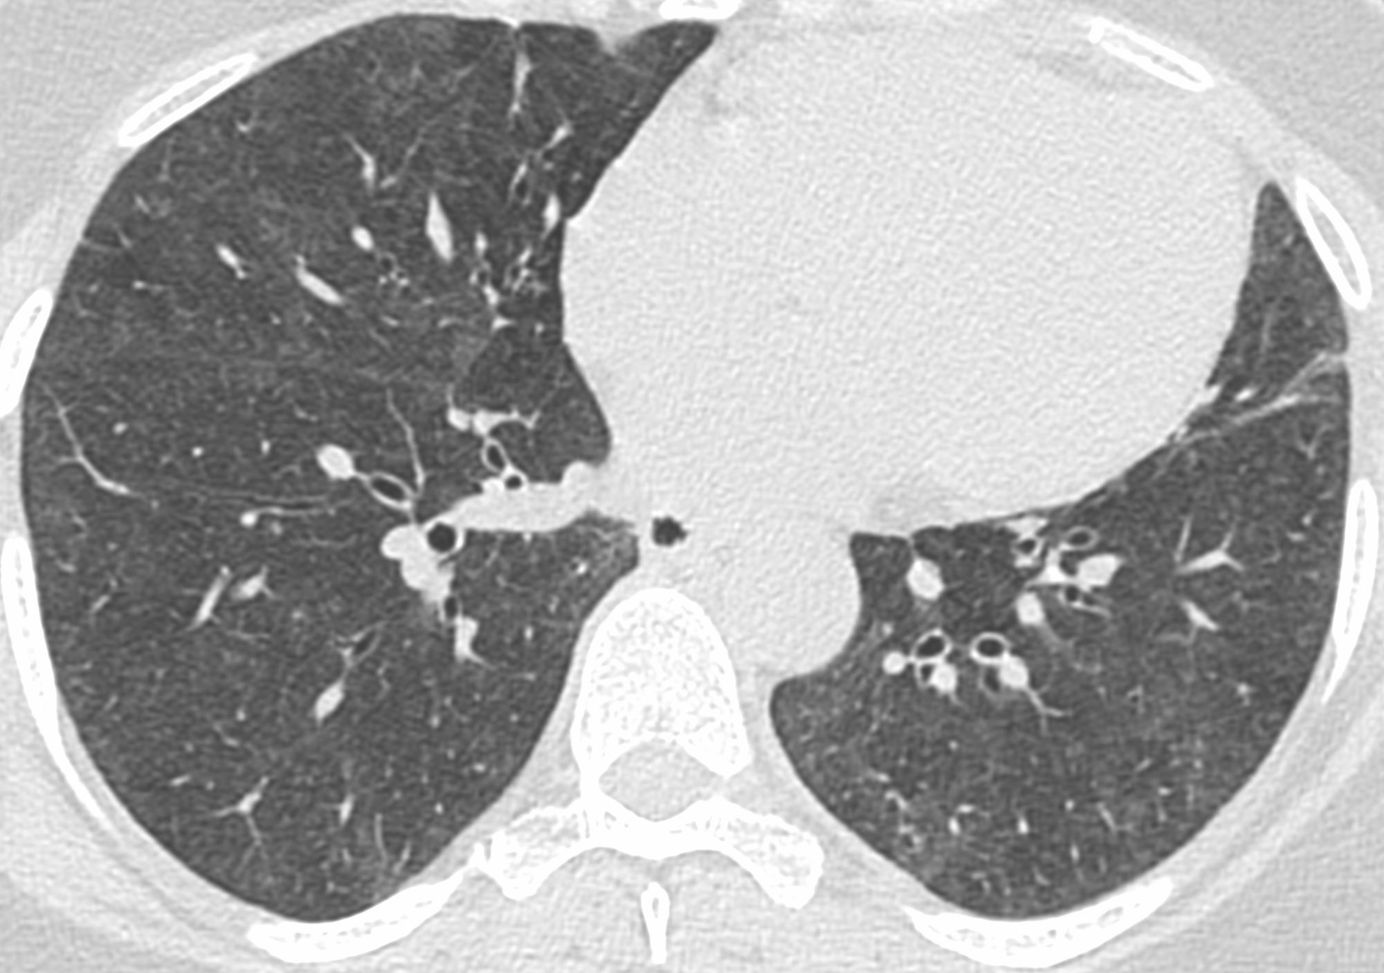

Case 17: Tuberculosis and Hemoptysis - Dense and Soft Centrilobular Nodules Together Members Public

17-years old with tuberculosis and hemoptysis - dense and soft centrilobular nodules together.